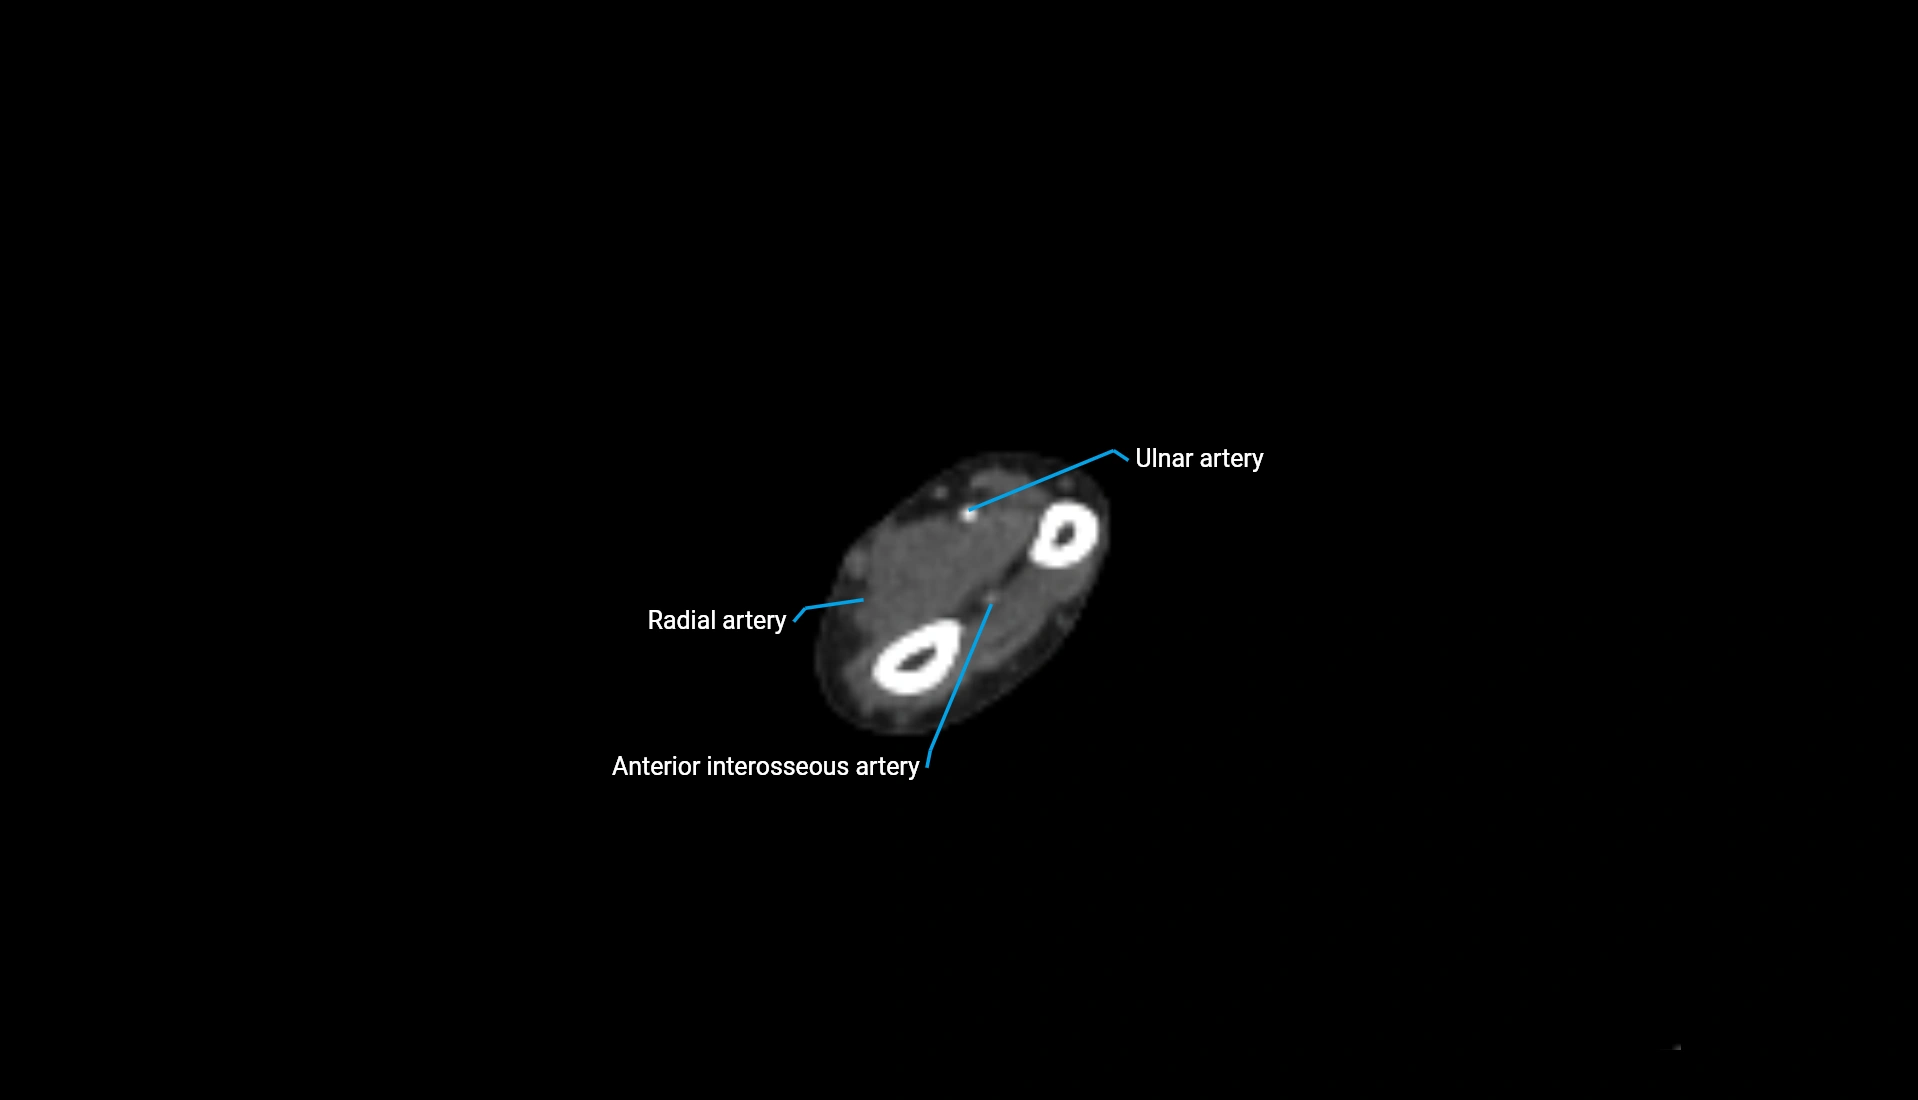

CT Appearance

Non-Contrast CT:

• Cortex: High-density, sharply defined

• Subchondral bone: Dense cancellous matrix

• Articular surface: Smooth concave contour articulating with the capitellum

• Excellent for evaluating bone integrity, alignment, and subtle fractures

Post-Contrast CT:

• Bone: No enhancement

• Joint capsule and synovium: Mild enhancement outlining the joint

• Improves contrast between soft tissues and bony margins

• Useful in detecting subtle joint abnormalities or postoperative changes